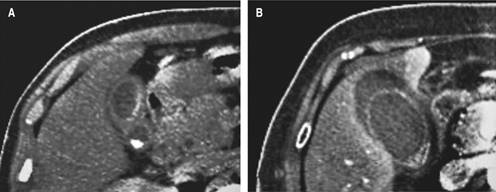

Upon admission, all patients underwent imaging studies for suspected acute cholecystitis (abdominal ultrasonography and or abdominal tomography). In all patients, the gallbladder wall thickening of more than 5 mm (mean: 8.96 mm, range: 5-16 mm) was corroborated, and signs of acute cholecystitis (criteria TG-18) or structural alterations were ruled out. Differences between acute cholecystitis and gallbladder edema in the abdominal ultrasound are shown in Figure 1, and differences in the CT scan are shown in Figure 2, respectively.

Figure 2: Tomographic differences between typical cholecystitis and simple gallbladder wall thickening. A) Typical cholecystitis gallbladder wall thickening. B) Gallbladder edema in a patient with viral disease without cholecystitis.